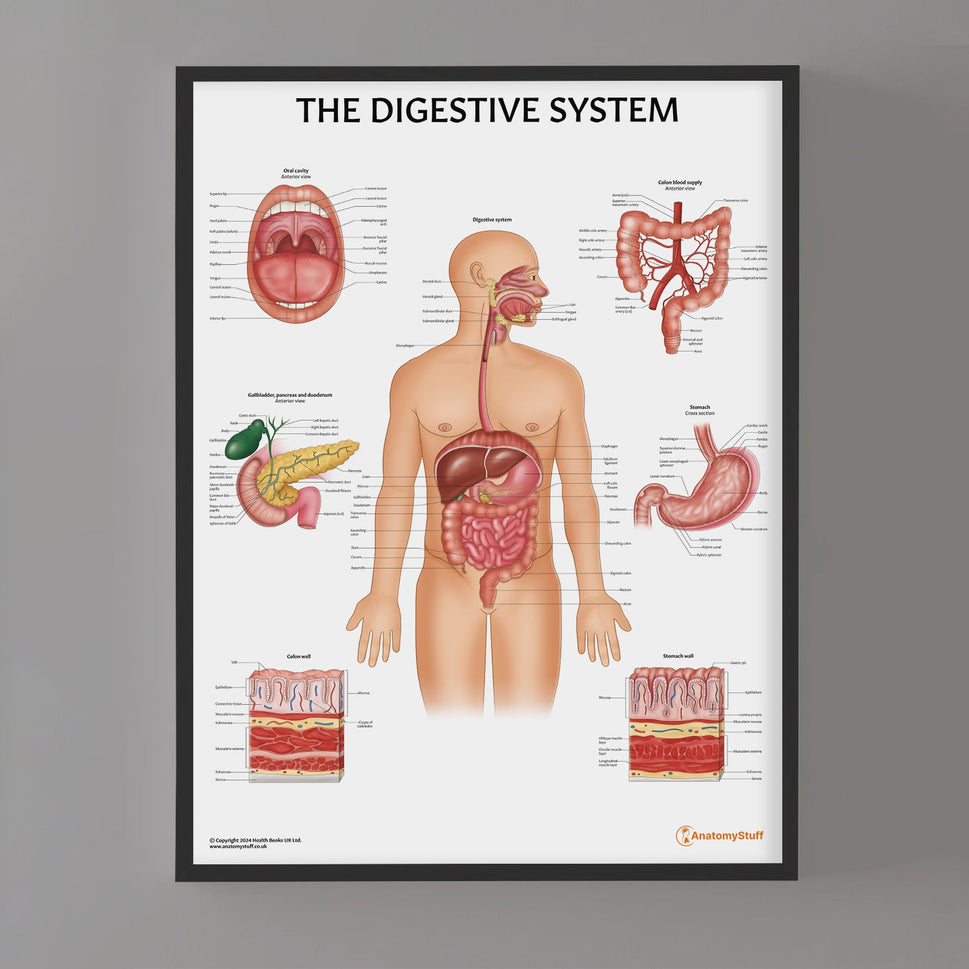

Enhance medical education with our collection of digestive system anatomical models including the stomach, liver, gallbladder, pancreas & colon models. Discover the anatomy of healthy organs as well as common gastrointestinal diseases such as stomach ulcers, gallstones and liver cirrhosis. Our digestive system anatomy posters are ideal for study and patient education.

At AnatomyStuff we stock a diverse range of digestive system anatomical models to suit your training needs. From budget models and affordable medical education posters to highly advanced 3D printed bowel models, you can transform medical training and patient education. As well as our own exclusive collection, we are proud resellers of 3B Scientific, Anatomy Lab, Denoyer-Geppert Science Company, ESP Models, Erler Zimmer and GPI Anatomicals. Explore our exclusive collection of digestive system anatomy charts, posters, fine art prints and digital anatomy study guides. Discover the anatomy of key organs like the liver, stomach, pancreas and bowel as well as the pathophysiology of common conditions like peptic ulcer disease, coeliac disease, IBD and much more. We have anatomy posters suitable for school children all the way up to medical degree level. From a liver anatomy poster to a digital study guide all about common GI disorders, find exactly what you need right here to enhance medical training and patient education.